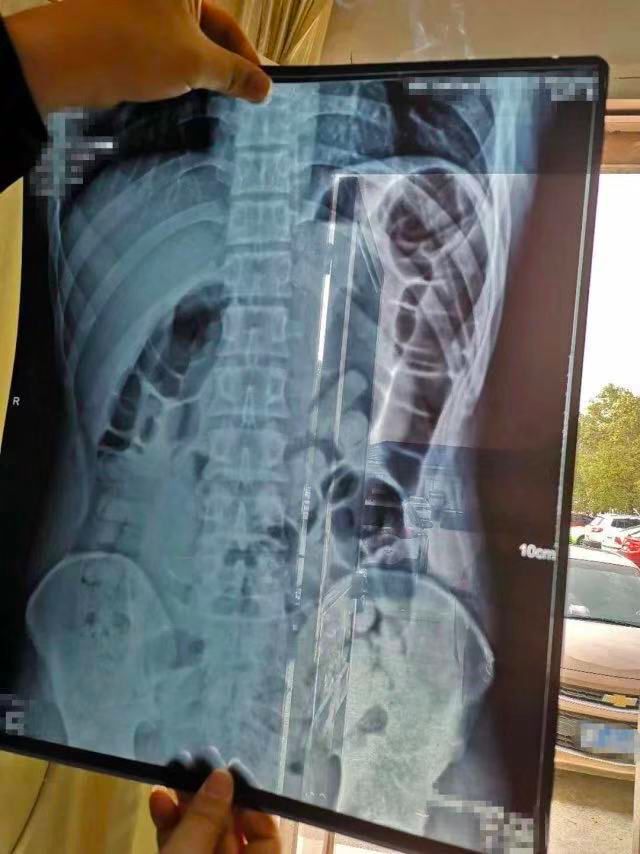

狱警向约翰逊展示囚犯身体的扫描图

图源|EPA-EFE

约翰逊看的就是这张囚犯的身体扫描图,

图中鸡蛋状的物品装满了*麻大**,

被塞入囚犯的臀部。